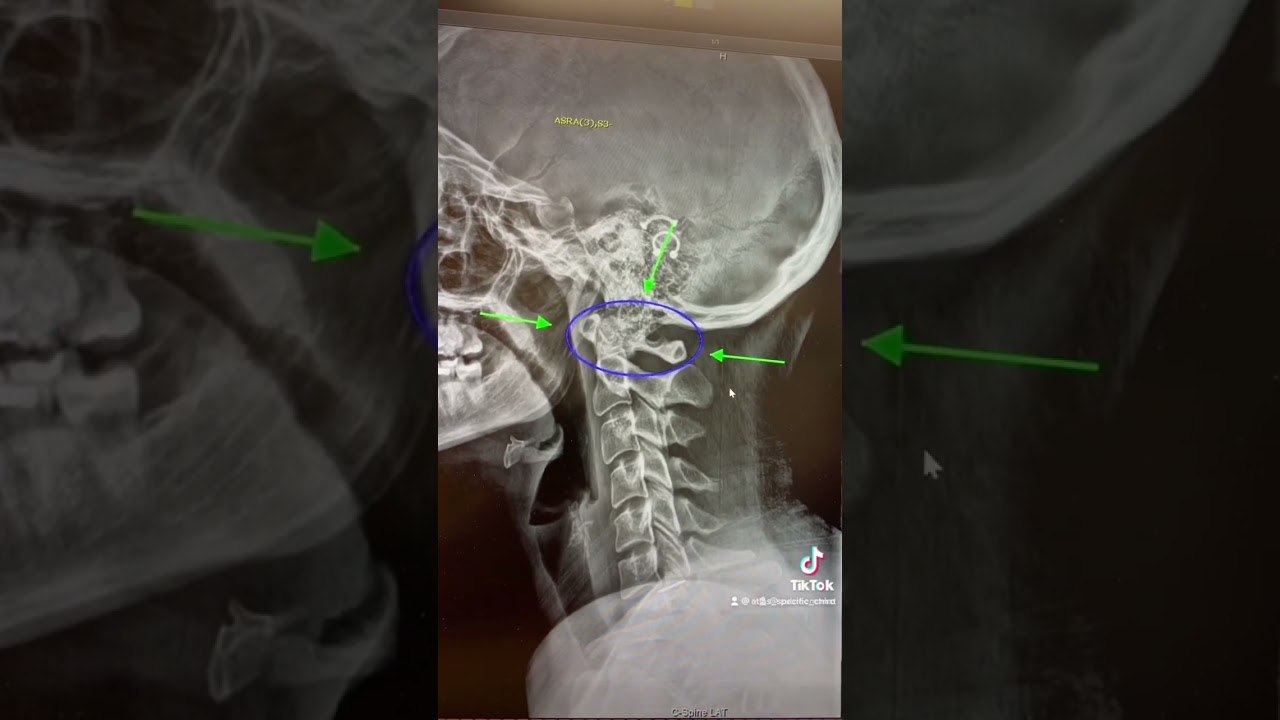

Identifying the Issue: Atlas Misalignment

Acknowledging that the problem stems from an atlas misalignment and understanding its implications.